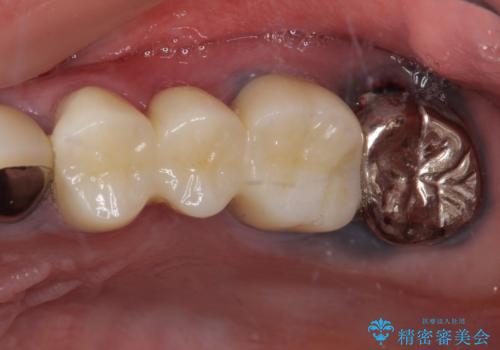

冷たいものがしみて奥歯が痛い 気になる歯並びも治した